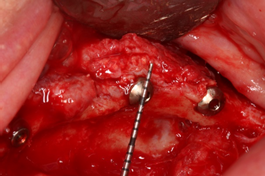

O implante Maestro tem se demonstrado como uma excelente opção em pacientes com baixa qualidade óssea, como também em regiões onde foram realizados procedimentos de enxertia óssea. Para a reabilitação desse caso clínico específico, os implantes Maestro Cone Morse e HI foram escolhidos devido às suas características diferenciadas de macrogeometria, aliadas ao seu tratamento de superfície. As câmaras de cicatrização incorporadas na macrogeometria dos implantes Maestro apresentam uma evidente aceleração no processo de osseointegração, bem como na qualidade desse processo 7,8. O design do implante favorece sua inserção com baixo torque, o que é essencial em regiões enxertadas. Os implantes foram instalados com torques de travamento primário variando entre 10 e 25 N (Figuras 5 a 8).

Após quatro meses, procedeu-se à cirurgia de reabertura e instalação dos pilares mini cônicos da linha de prótese do sistema CM e HI da Implacil De Bortoli e a paciente foi encaminhada para o protesista para instalação das próteses tipo protocolo. Nas figuras 9, 10 e 11 podemos observar o acompanhamento radiográfico e clínico após dois anos de follow-up.